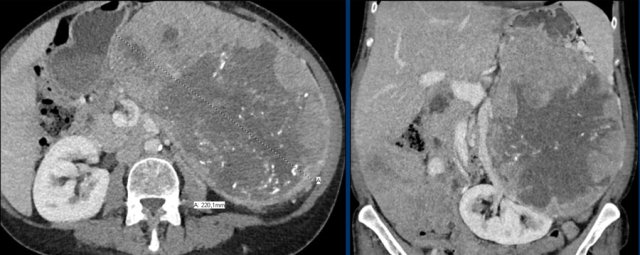

Here a large right adrenal adrenal carcinoma with extensive abdominal and mediastinal para-aortic lymph node metastases at the time of diagnosis.

Axial venous phase CT in mediastinal and bone window setting Axial venous phase CT in mediastinal and bone window setting

Images depict mediastinal and bone window setting of a patient with a bulky heterogeneously enhancing right adrenal tumor.

This was proven to be an adrenocortical carcinoma.

There is a faint, ill-defined liver lesion in segment 6 and there are non-specific sclerotic changes in the body of T12.

Continue with the PET-image...

PET-CT performed for complete staging shows intense uptake in the adrenal tumor, indicative of its malignant nature.

There is also intense uptake in two liver metastases and in a bone metastasis in T12.

Approximately 20-40% of patients with an adrenocortical carcinoma present with metastases at diagnosis.

This axial venous CT shows a very bulky right adrenal mass, suspicious for a malignancy, based on the large size and heterogeneity.

This lesion is an adrenocortical carcinoma, but in contrast to the former example, subsequent FDG PET-CT performed for staging purposes showed only mild uptake and only in the most avidly enhancing part of the tumor.

Most adrenocortical carcinomas show intense FDG-uptake.

This lack of FDG-avidity might be due to a lower grade tumor with lower mitotic rate or large hemorrhagic or necrotic components.